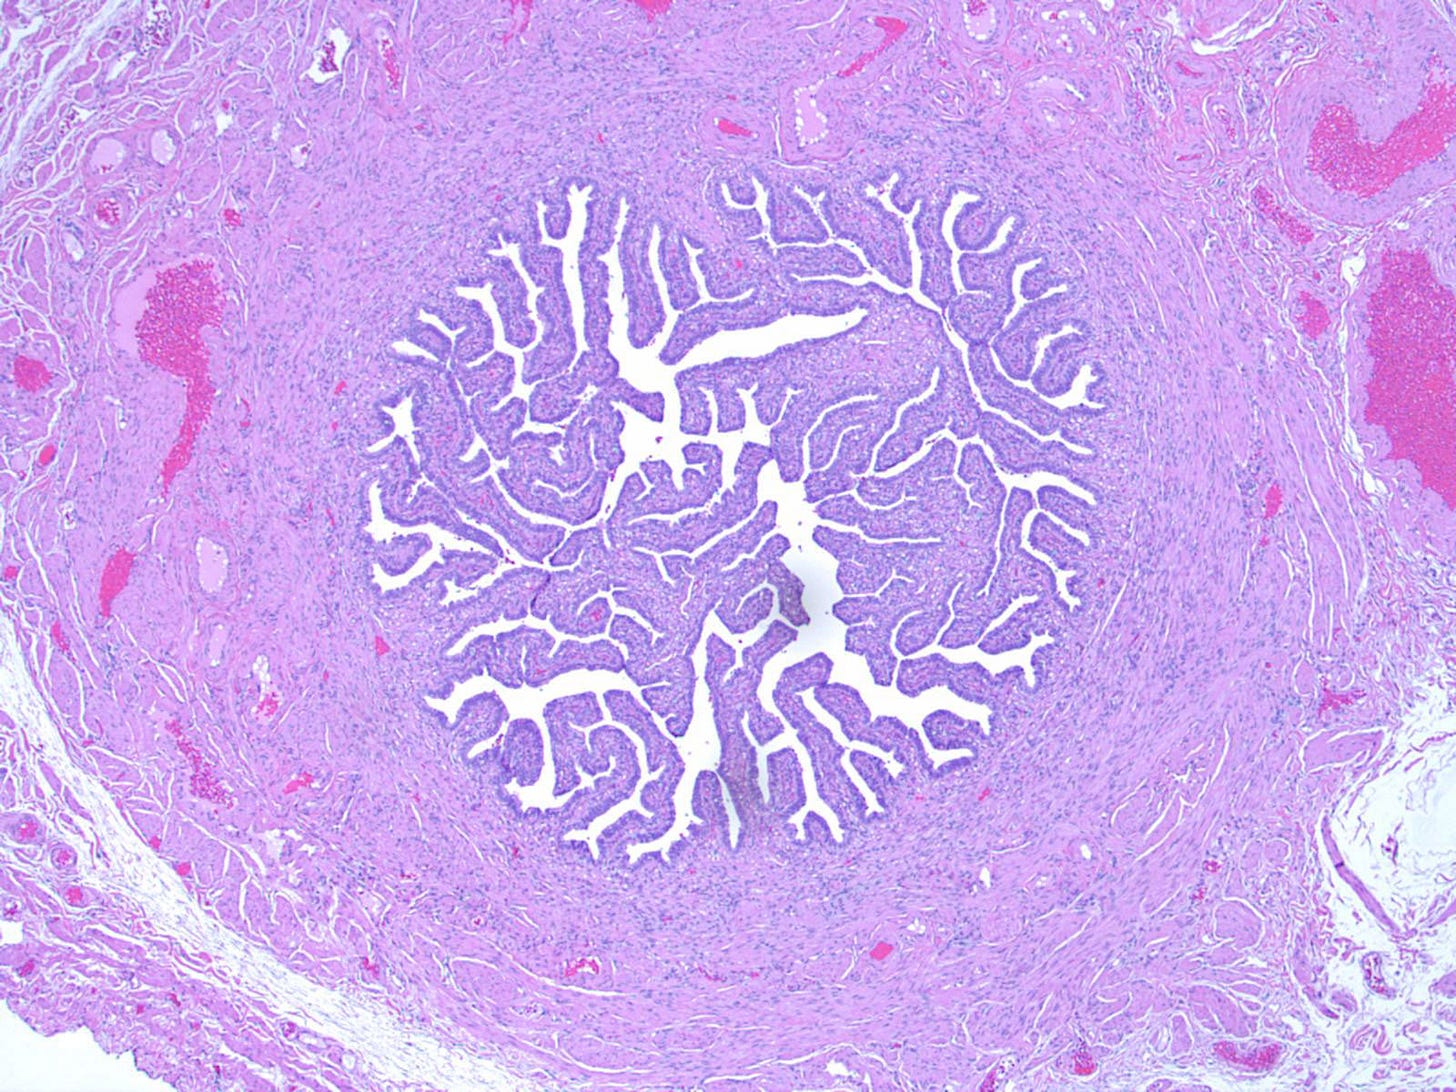

The fallopian tubes are hollow, tubular structures, bilateral, 8 - 12 cm long and 0.5 - 1.2 cm in diameter that extend from the posterior of the uterus laterally towards the ovaries.

Most ovarian cancers are epithelial, but most testicular tumors derive from germ cells or sex cord stroma. Many ovarian cancers arise, in fact, from the fallopian tubes or the uterus, not from the ovaries themselves, as will be discussed in a future essay.